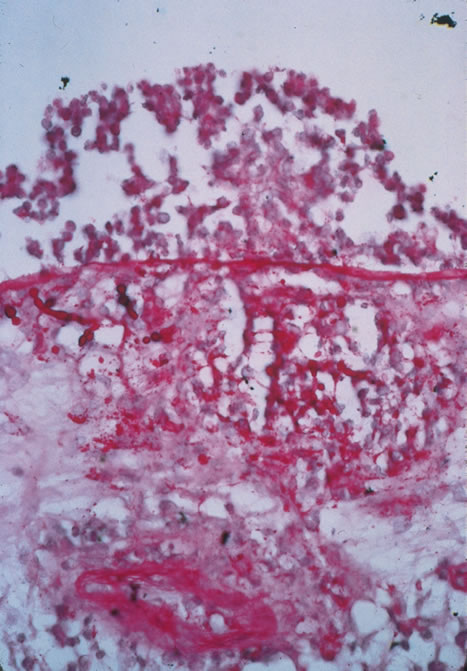

In primary ocular HSV infections, a severe follicular conjunctivitis with regional adenopathy is present. Vesicles may appear on the eyelid skin or lid margin, producing blepharitis (Fig. 3). Corneal involvement initially takes the form of a superficial punctate keratitis, which may progress to dendritic or geographic ulceration. Stromal infiltrates and uveitis are less common and relatively mild in primary disease. In uncomplicated cases, lesions usually heal completely in 2 to 3 weeks without scarring. Most cases of ocular HSV are recurrences. Recrudescent ocular herpes may take the form of dendritic or geographic ulcers, recurrent erosions, interstitial or disciform stromal keratitis, and anterior uveitis.3 HSV may also be an agent of retinitis and acute retinal necrosis (Fig. 4).